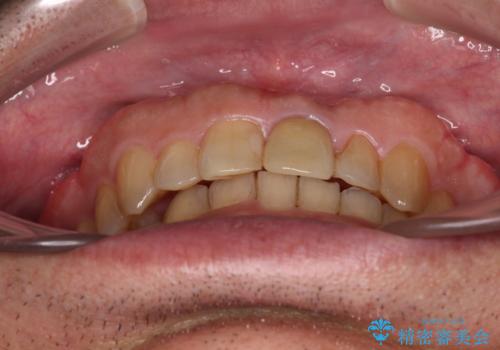

- 上下前歯のデコボコと下顎小臼歯の欠損によるスペースを気にして来院された患者様です。

下顎は左右1本ずつ小臼歯が欠損しており、右側にはやや大きな欠損がありました。

欠損により下顎歯列は相対的に小さく、上顎に深く咬みこんでしまうディープバイトとなっていました。

インビザラインによる治療を希望されたため、左側のスペースは閉じ、右側はスペースをより拡大し、インプラント補綴を行うこととしました。